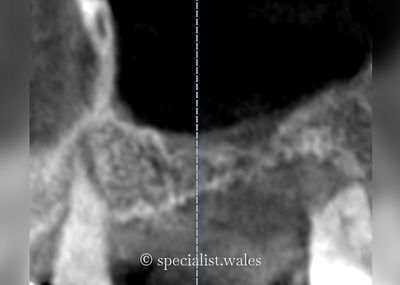

Above your molar and premolar teeth in the upper jaw on both sides lies a cavity called the maxillary sinus, or maxillary antrum. If you loose a tooth below the maxillary sinus, once the bone has healed where the tooth used to be, sometimes there is no longer adequate height of bone in which to place a dental implant in to. The most predictable technique to generate extra bone height is to perform a sinus lift. This involves making a small window in the side of the sinus above where the tooth is to be replaced. The thin membrane that lines the sinus, called the Schneiderian membrane, is then elevated to create a pocket into which a combination of graft material (bovine xenograft) and some autogenous bone (bone from yourself collected from the local area are placed. The window that was made is then covered with a porcine collagen membrane and then the gum stitched back together. We then wait a period of 6 to 9 months for the bone graft to heal and mature into a solid block of bone into which implants can safely be placed. This surgery is usually performed by Mr Mallorie under local anaesthetic with the addition of intravenous sedation to help make the process as comfortable as possible for his patients. Sometimes we are able to place the dental implant(s) at the same time as performing the sinus surgery to help reduce the overall treatment time and the number of surgeries required.